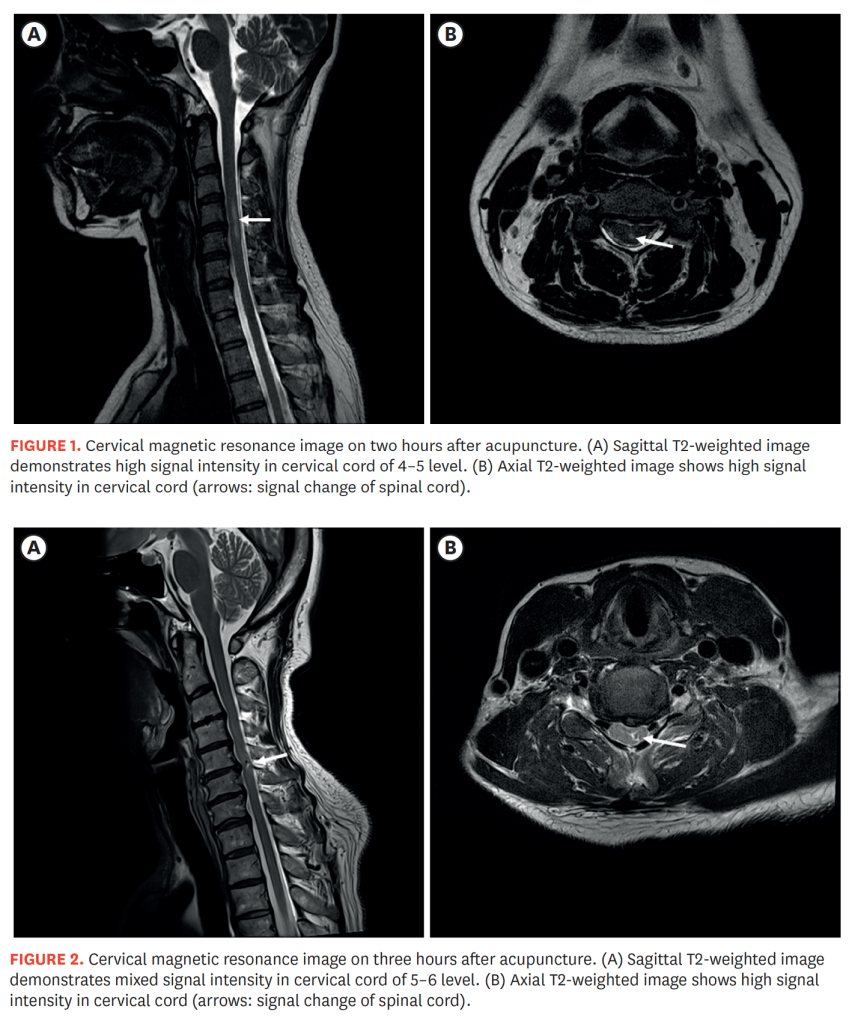

MR imaging (T2 weighted) demonstrated high signal intensity within the cervical spinal cord in both cases.

There are limited details of the acupuncture treatment, but the rapid onset of neurological signs following treatment combined with the imaging appearances, strongly suggest direct penetration of the spinal cord by an acupuncture needle in both cases.